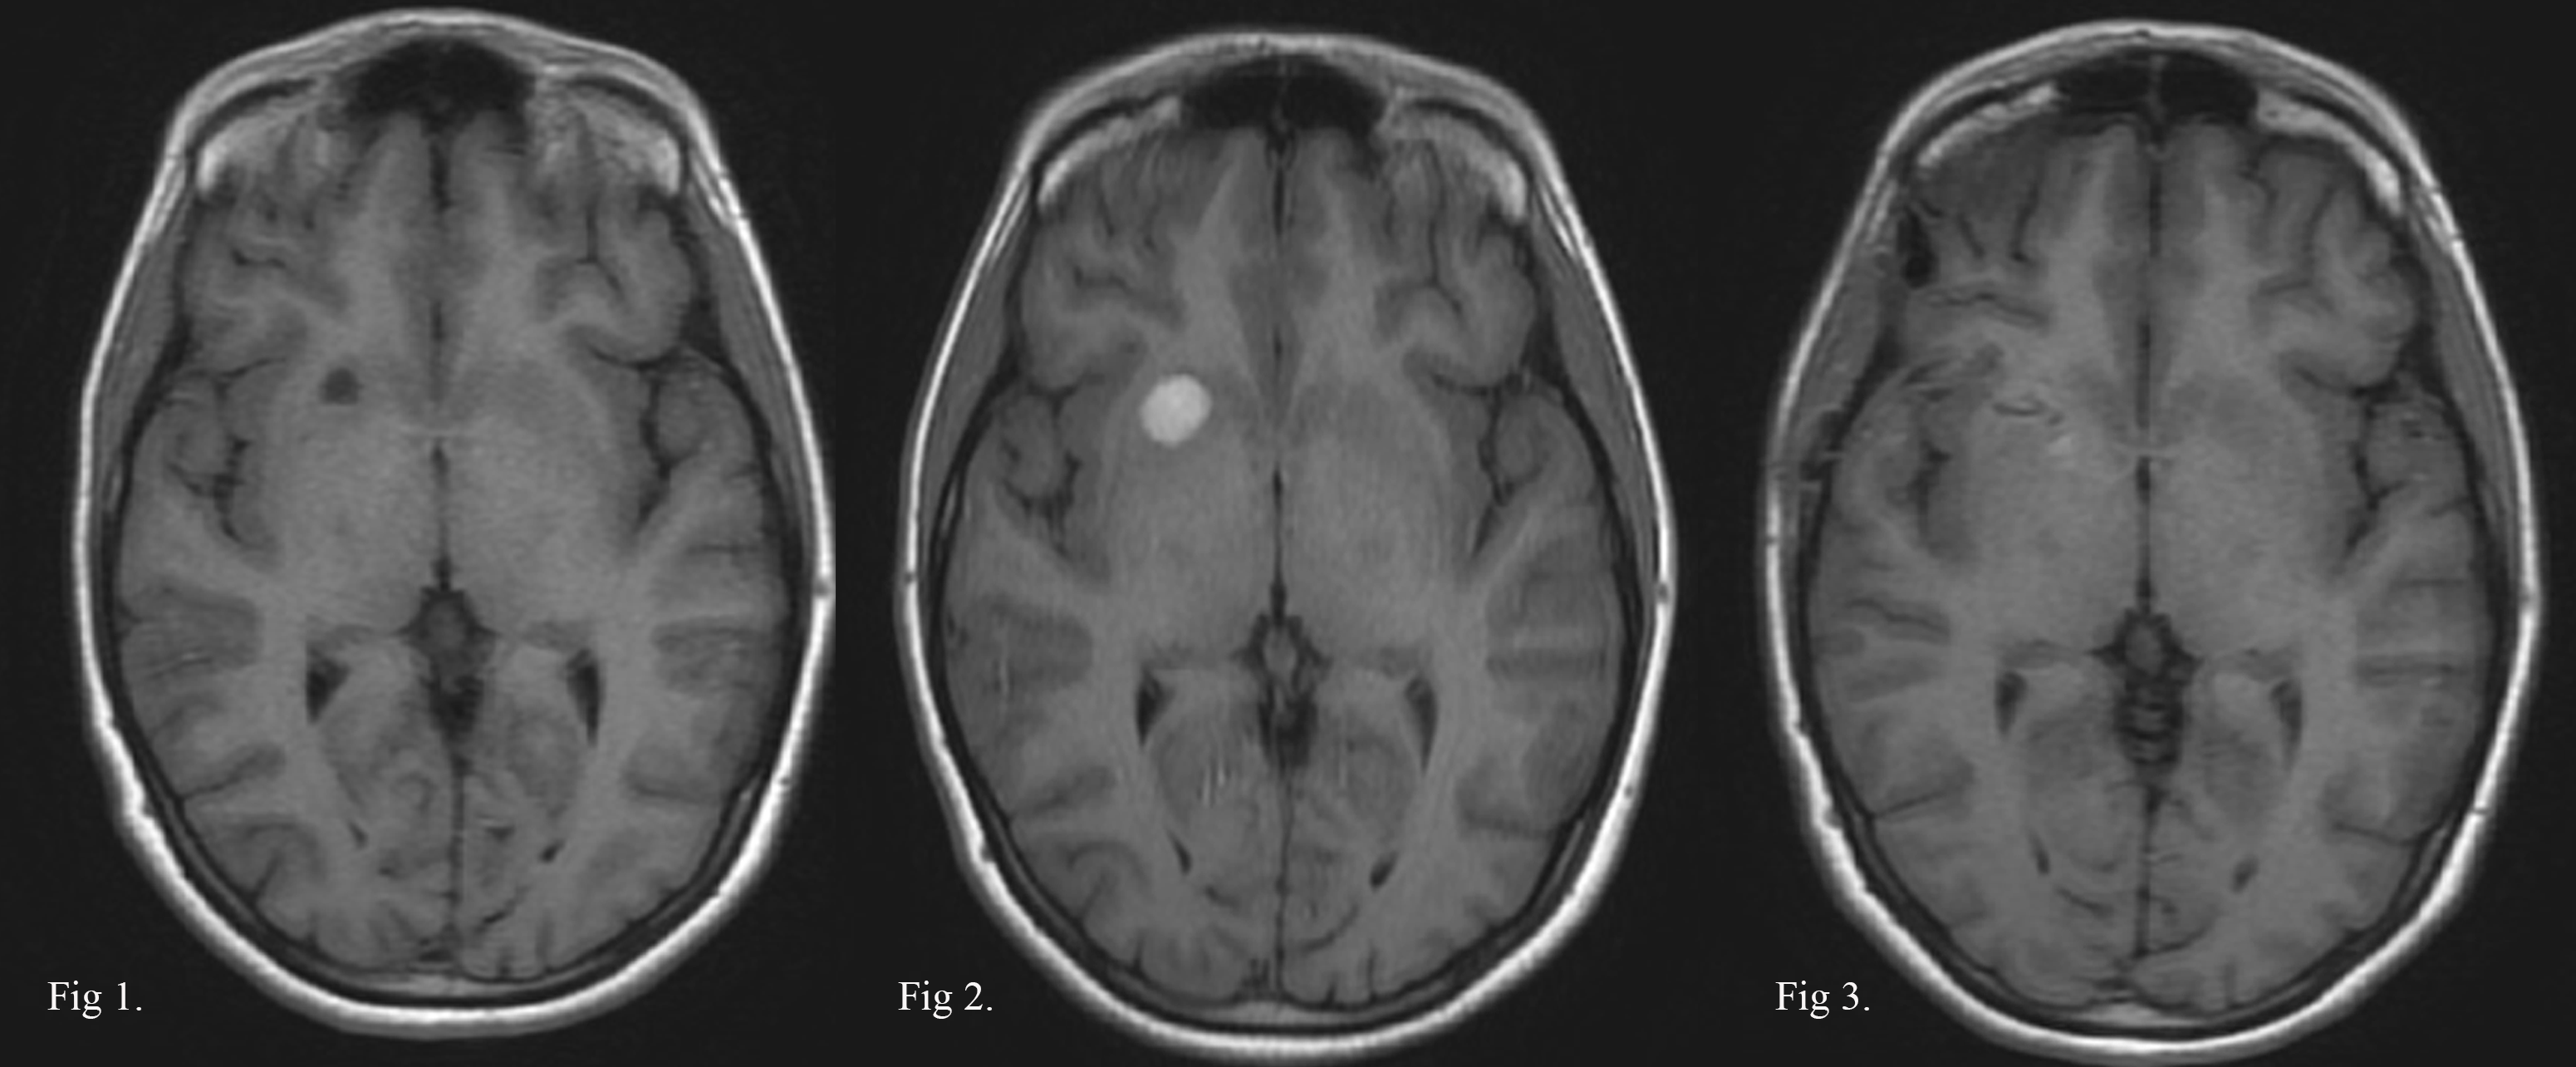

CASO EJEMPLO 1: CAVERNOMA INCIDENTAL LENTICULAR ANTERIOR DERECHO.

Fig 1: 2020: Mujer, 33 años, cavernoma incidental no complicado.

Fig 2: 2021: Persiste asintomática con hematoma intracapsular en RMN control.

Fig 3: 2021: RMN postop. de exéresis por vía transilviana trans-surco circular anterior de la ínsula.